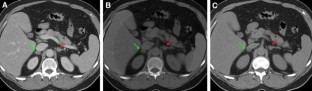

Technical improvements in the acquisition and display of dual-energy computed tomography (DECT) have made this technique increasingly applicable to clinical practice, particularly in the setting of oncologic imaging. DECT allows for qualitative and quantitative analysis of tissue composition beyond the standard anatomical evaluation possible with single-energy computed tomography. For example, DECT can be used to interrogate iodine and calcium concentrations and to increase iodine signal, which makes many pathologic processes more conspicuous and provides improved understanding of internal structure within mass lesions. A working understanding of common postprocessing DECT displays will allow radiologists to maximize the additional diagnostic information available in DECT examinations. In this article, we describe common strategies for DECT interrogation by organ system, which may improve the conspicuity and understanding of suspected malignancies.

Fig. 2